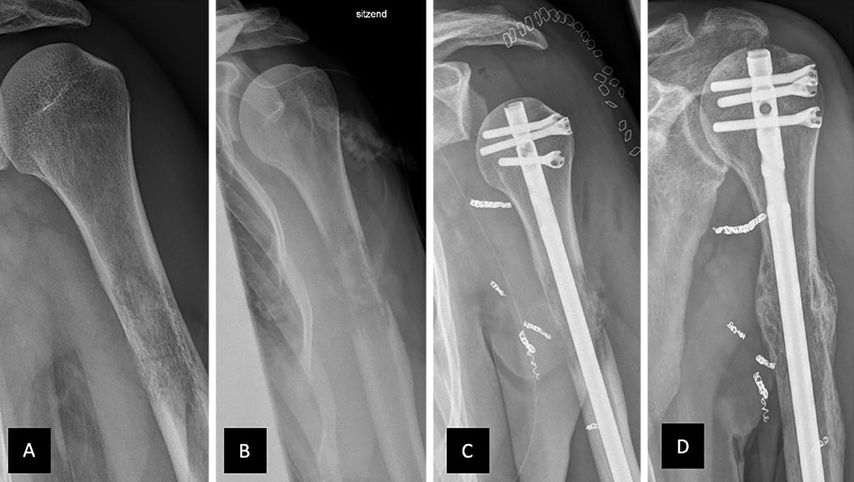

Abb. 3: Nagelosteosynthese bei Metastase eines Nierenzellkarzinoms. A,B) Metastase mit Destruktion der Kortikalis im Verlauf von ca. 4 Wochen; C) postoperatives Röntgenbild inkl. präoperativ eingebrachter Coils; D) 16 Wochen postoperativ bei Zustand nach Radiatio und guter Rekalzifizierung/Kallusbildung